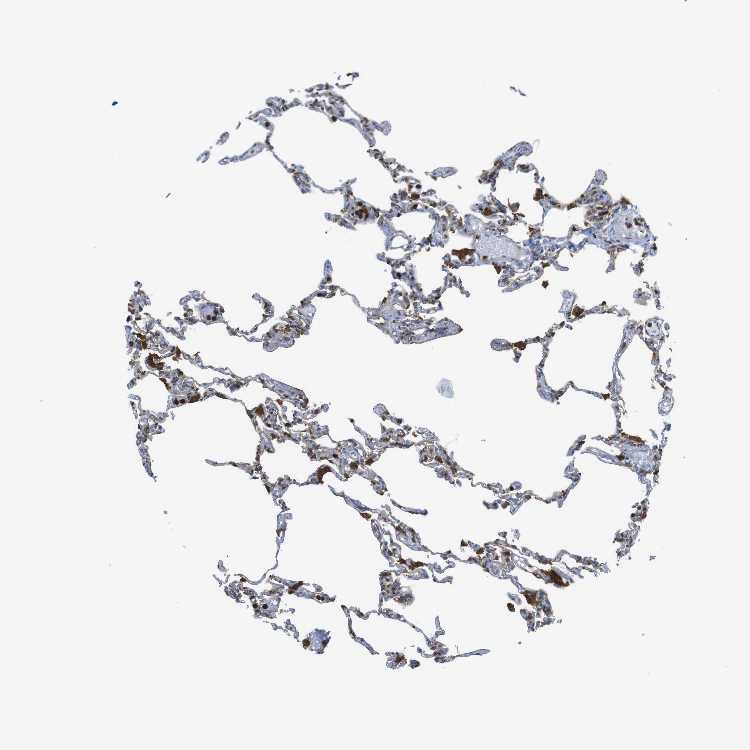

LUNG - Antibody stainingi

Antibody staining in the annotated cell types in the current human tissue is reported as not detected, low, medium, or high, based on conventional immunohistochemistry profiling in selected tissues. This score is based on the combination of the staining intensity and fraction of stained cells. Each image is clickable and will lead to virtual microscopy that enables deeper exploration of all samples and also displays staining intensity scores, fraction scores and subcellular localization as well as patient and tissue information for each sample.

Antibody HPA001863Antibody HPA001890Antibody CAB010469Antibody CAB013225

Alveolar cells HighMediumLow-

Alveolar cells type I ---Medium

Alveolar cells type II ---Medium

Endothelial cells ---Not detected

Macrophages HighHighHighHigh